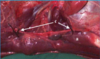

external ear opened to level of facial nerve